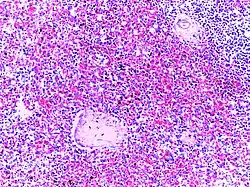

![]() |

Follicular lymphoma | Micrograph showing a small B-cell lymphoma compatible with follicular lymphoma. H&E stain. | Category: Histopathology of follicular lymphoma | Follicular lymphoma |